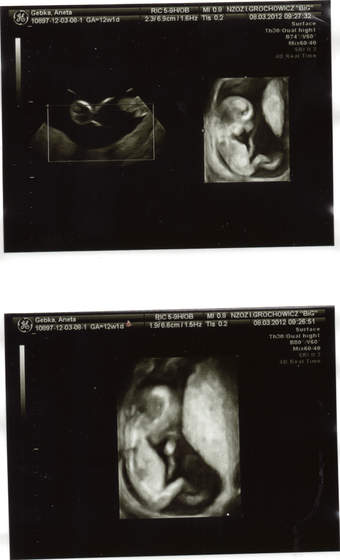

Jestem juz po wizycie :-) wszystko w jak najleprzym porzadku .Wszystkie wymiary i przepływy książkowe pępowina prawidłowa łozysko tez wielkosc ciazy 12/13 tydz .Płec nie wiadomo lekarz powiedział ze nie bedzie zgadywac bo nie widac .Miesniaków jest kilka ,jeden duzy reszta mała nie rosną i sa tak umiejscowione ze nie przeszkadzają dzidzi.A mamusia mega szczesliwa.

A teraz foto

Zobacz załącznik 444755